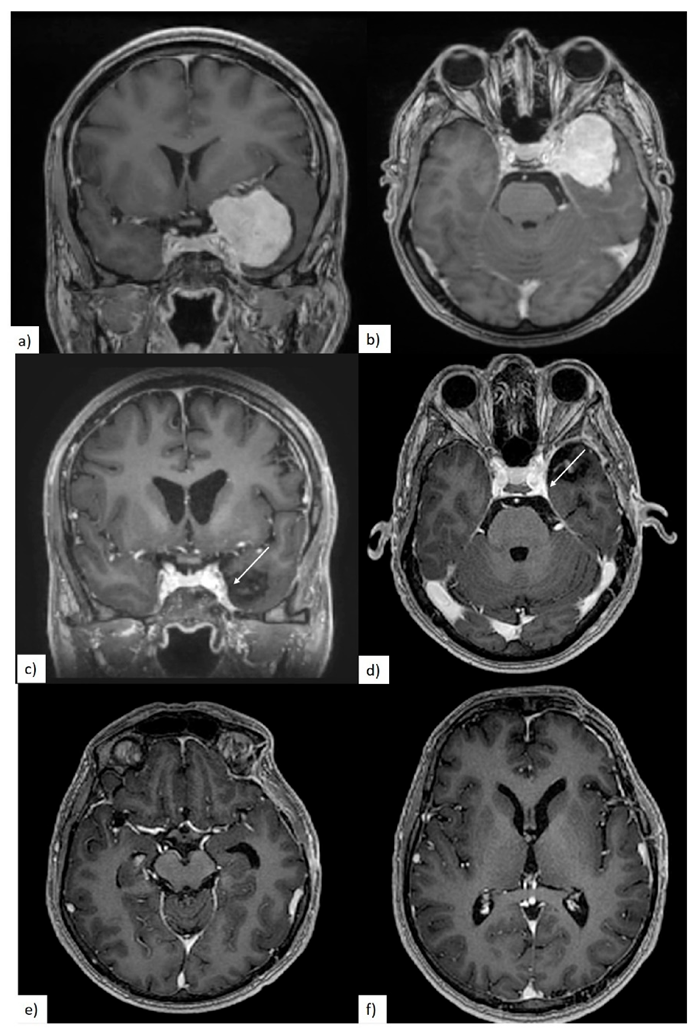

3.2. Preoperative Clinical and Radiological Data

3.3. Quality of Resection

3.4. Postoperative Clinical Evolution and Follow-up